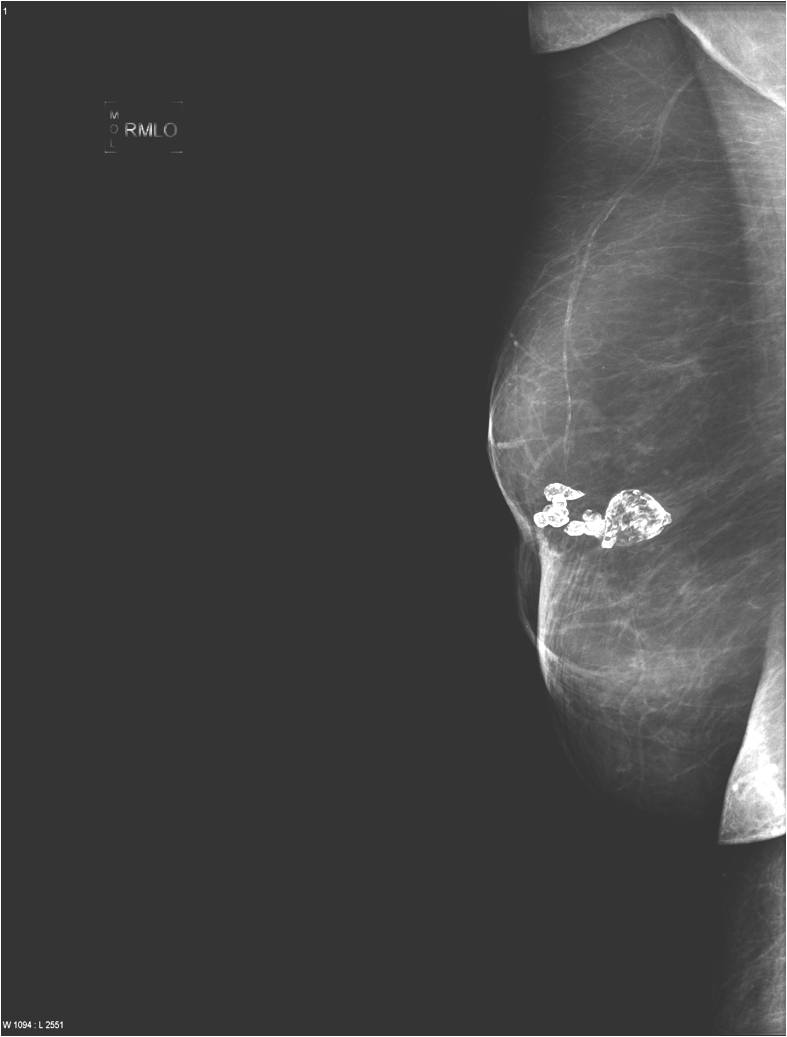

Calcifications are encountered in the breast quite often. Most of them accompany benign process (Picture 21.) and only a smaller percentage actually indicates malignancy. These malignant signs are basically always micro-calcifications. They are ill-shaped, with various pleomorphism (Pictures 23.,24.) and they are usually show a clustered arrangement. Their number is irrelevant to the grade of malignancy. Their analysis with mammography is often hard, but targeted and magnified images can help in it. In most the cases these lesion can’t be identified with ultrasound, so stereotaxy core biopsy is needed.

Image

Picture 21.

Picture 22.

Picture 23.

Picture 24